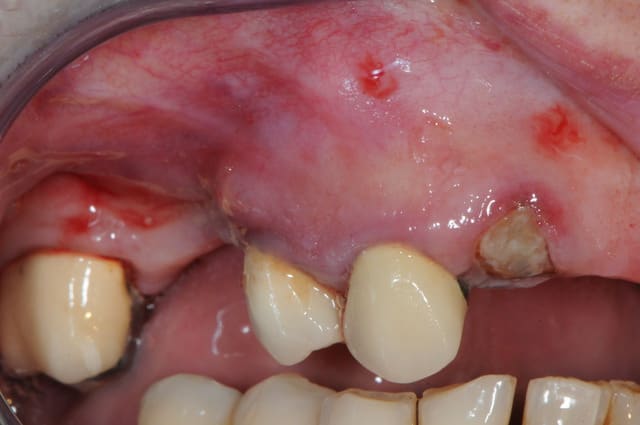

je poste ici les photos de ce matin pour la maman d'Aurélie.

du coup j'en fais profiter tous le monde...

14 était fracturée et il y avait une infection +++ au niveau de la 15 avec perte de la table vestibulaire.

j'ai mis du bioos et membrane collagène AT résorbable fixée par trois pins.

le port de la prothèse est contre-indiqué pendant 2 mois ou alors avec un sérieux évidement de l'intrados.

elle a eu le plus dure. la pose des implants plus tard,ça sera du gâteau.